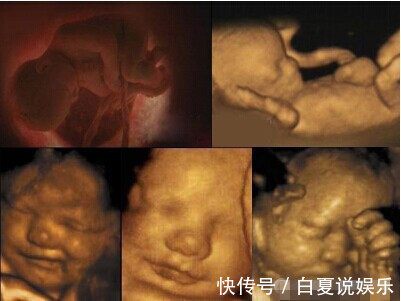

当医生了解情况后,突然就笑了起来,这令丽姐一家人更加紧张,随后医生说:对于怀孕8个月的孕妇来说,这种情况很常见,因为这个阶段的胎儿几乎发育完全,更有了听觉和触觉,虽然还在腹中,还有羊水保护,但在安静的环境下,如果胎儿发出声音,对于准妈妈来说还是能够感觉到的。知道原来是这个情况后,丽姐也不好意思的笑了起来,还是对育儿方面的知识了解不多啊。

其实各位准妈妈也要注意,如果孕期出现不正常情况,应该第一时间去医院检查,特别是听到胎儿哭声,这很有可能是宝宝在像你求救。而丽姐做完检查后,原来是胎儿脐带打结,造成宝宝缺氧,从而妈妈就听到了孩子哭声。这也是不幸中的万幸啊。